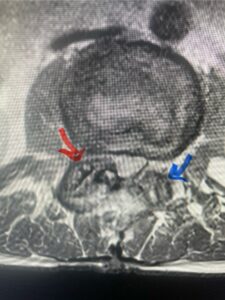

This 61-year-old female with a history of severe osteoporosis and a prior history of a laminectomy from l2-S1 with an L5-S1 instrumented fusion, presents with progressive low back pain and right lower extremity radiculopathy. MRI revealed a grade 1 L2-3 spondylolisthesis with severe stenosis mainly from severe right L2-3 facet joint hypertrophy which was compressing the right L3 descending nerve root. (Fig. 1). She had failed conservative management consisting of physical therapy and pain management with epidurals. She underwent an L1-3 revision laminectomy where we had to dissect a plane underneath the inferior aspect of the L2 lamina. We performed an instrumented fusion at L2-3 with special hydroxyapatite-coated screws to improve fixation to surrounding bone given here severe osteoporosis (Fig. 2) This worked out well and the patient had an uneventful recovery with relief of her leg pain.

Fig: 2a: AP and lateral intraoperative fluoroscopic images demonstrating good placement of L2-3 pedicle screws